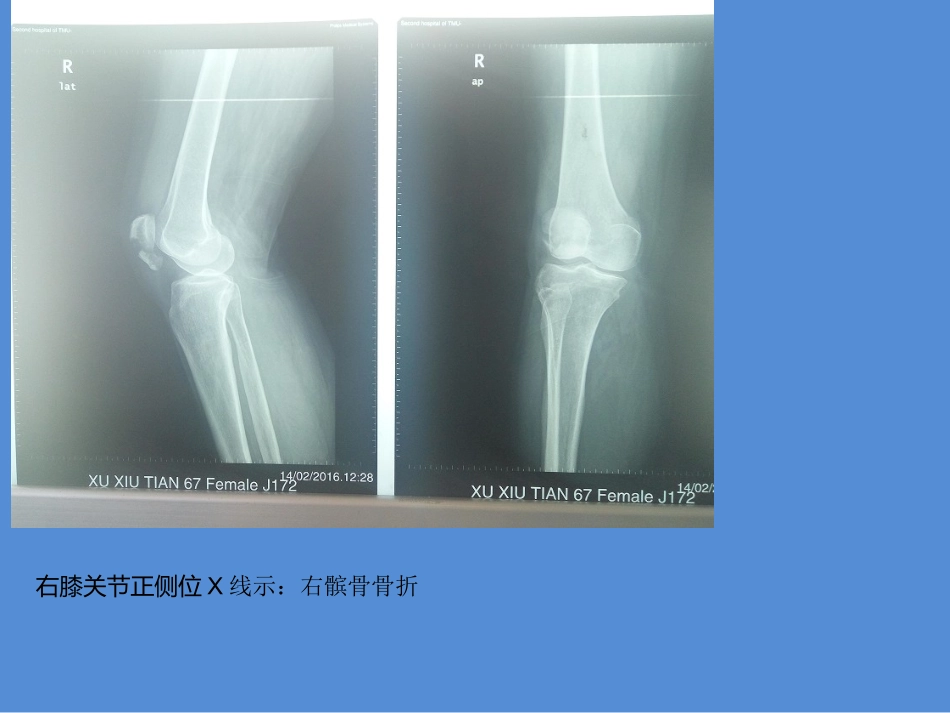

病例汇报患者女,62岁,主因“摔伤致右膝部疼痛伴活动受限2小时”入院。查体:右膝部肿胀,压痛,膝关节活动受限。高血压病史,最高180/140,自服罗布麻,控制可。肾动脉狭窄支架术后。过敏史:磺胺药物过敏。右膝关节正侧位X线示:右髌骨骨折右膝关节正侧位X线示:右髌骨骨折诊断:1.右髌骨骨折2.高血压3.双肾动脉狭窄支架成形术后4/10患者在CEA下行“右髌骨骨折切开复位内固定术”,术程顺利,术后安返病房,予对症支持治疗,伤口定期换药,愈合良好,无明显红肿渗出。1.꼭꼭꼭꼭-꼭꼭꼭꼭꼭꼭내내내내내내내내내내내내내내내내내내내내내내내내내내5/10复查右膝平片:髌骨骨折端对位良好6总结:髌骨骨折是常见的关节内骨折,其发生率约占全身各部位骨折的1%髌骨作用:一方面,作为伸膝装置的中间结构,它将股四头肌产生的拉力传向髌腱;另一方面,髌骨有效的增加了伸膝装置对于膝关节屈伸轴点的杠杆力臂,这样就增大了股四头肌的力矩,加强其机械效益。6/10Ⅰ型:骨折无移位或移位距离<5mm,髌骨关节面移位<2mm,或虽有移位,但骨折位于髌骨下极且未涉及关节面。Ⅱ型:骨折为2块,呈横形、斜形或纵形,位于髌骨体中部,移位距离≥5mm,髌骨关节面移位≥2mm。Ⅲ型:粉碎性骨折,移位距离≥5mm,髌骨关节面移位≥2mm。8/10手术指征:骨折分离3~4mm及关节面不平2~3mm可以接受非手术治疗;如果分离移位或关节面不平超过此范围,则有手术指征。1.环形缝扎传统方法,常用材料为粗丝线及钢丝。使骨折块向髌骨中心聚集,对抗髌骨周围的张力,达到复位、固定之目的。此方法适用于髌骨粉碎骨折或有分离移位的髌骨中段横行骨折。优点:简易,经济。缺点:并发症多。1.环形缝扎传统方法,常用材料为粗丝线及钢丝。使骨折块向髌骨中心聚集,对抗髌骨周围的张力,达到复位、固定之目的。此方法适用于髌骨粉碎骨折或有分离移位的髌骨中段横行骨折。优点:简易,经济。缺点:并发症多。2.改良式张力带将张力带钢丝放在髌骨中段周围,当屈膝时,折块前部即分离,形成张力。若钢丝置于髌前,以克氏针作为钢丝固定点,穿过股四头肌腱和髌韧带,所有张力都被抵消,骨骼处于单纯压应力之下,可允许早期活动锻炼,且不需外固定。此方法适用于有分离移位的髌骨中段横行骨折。优点:吸收张力,使骨骼承受压力。。缺点:克氏针引起的软组织疼痛,关节活动度差。12手术并发症伤口愈合不良感染:多见于开放性骨折12/1013创伤性骨关节炎:创伤性关节炎是髌骨骨折较为常见的并发症。注意合并伤的处理及术后积极功能锻炼,可减少创伤性关节炎发生。13/1014谢谢!14/10